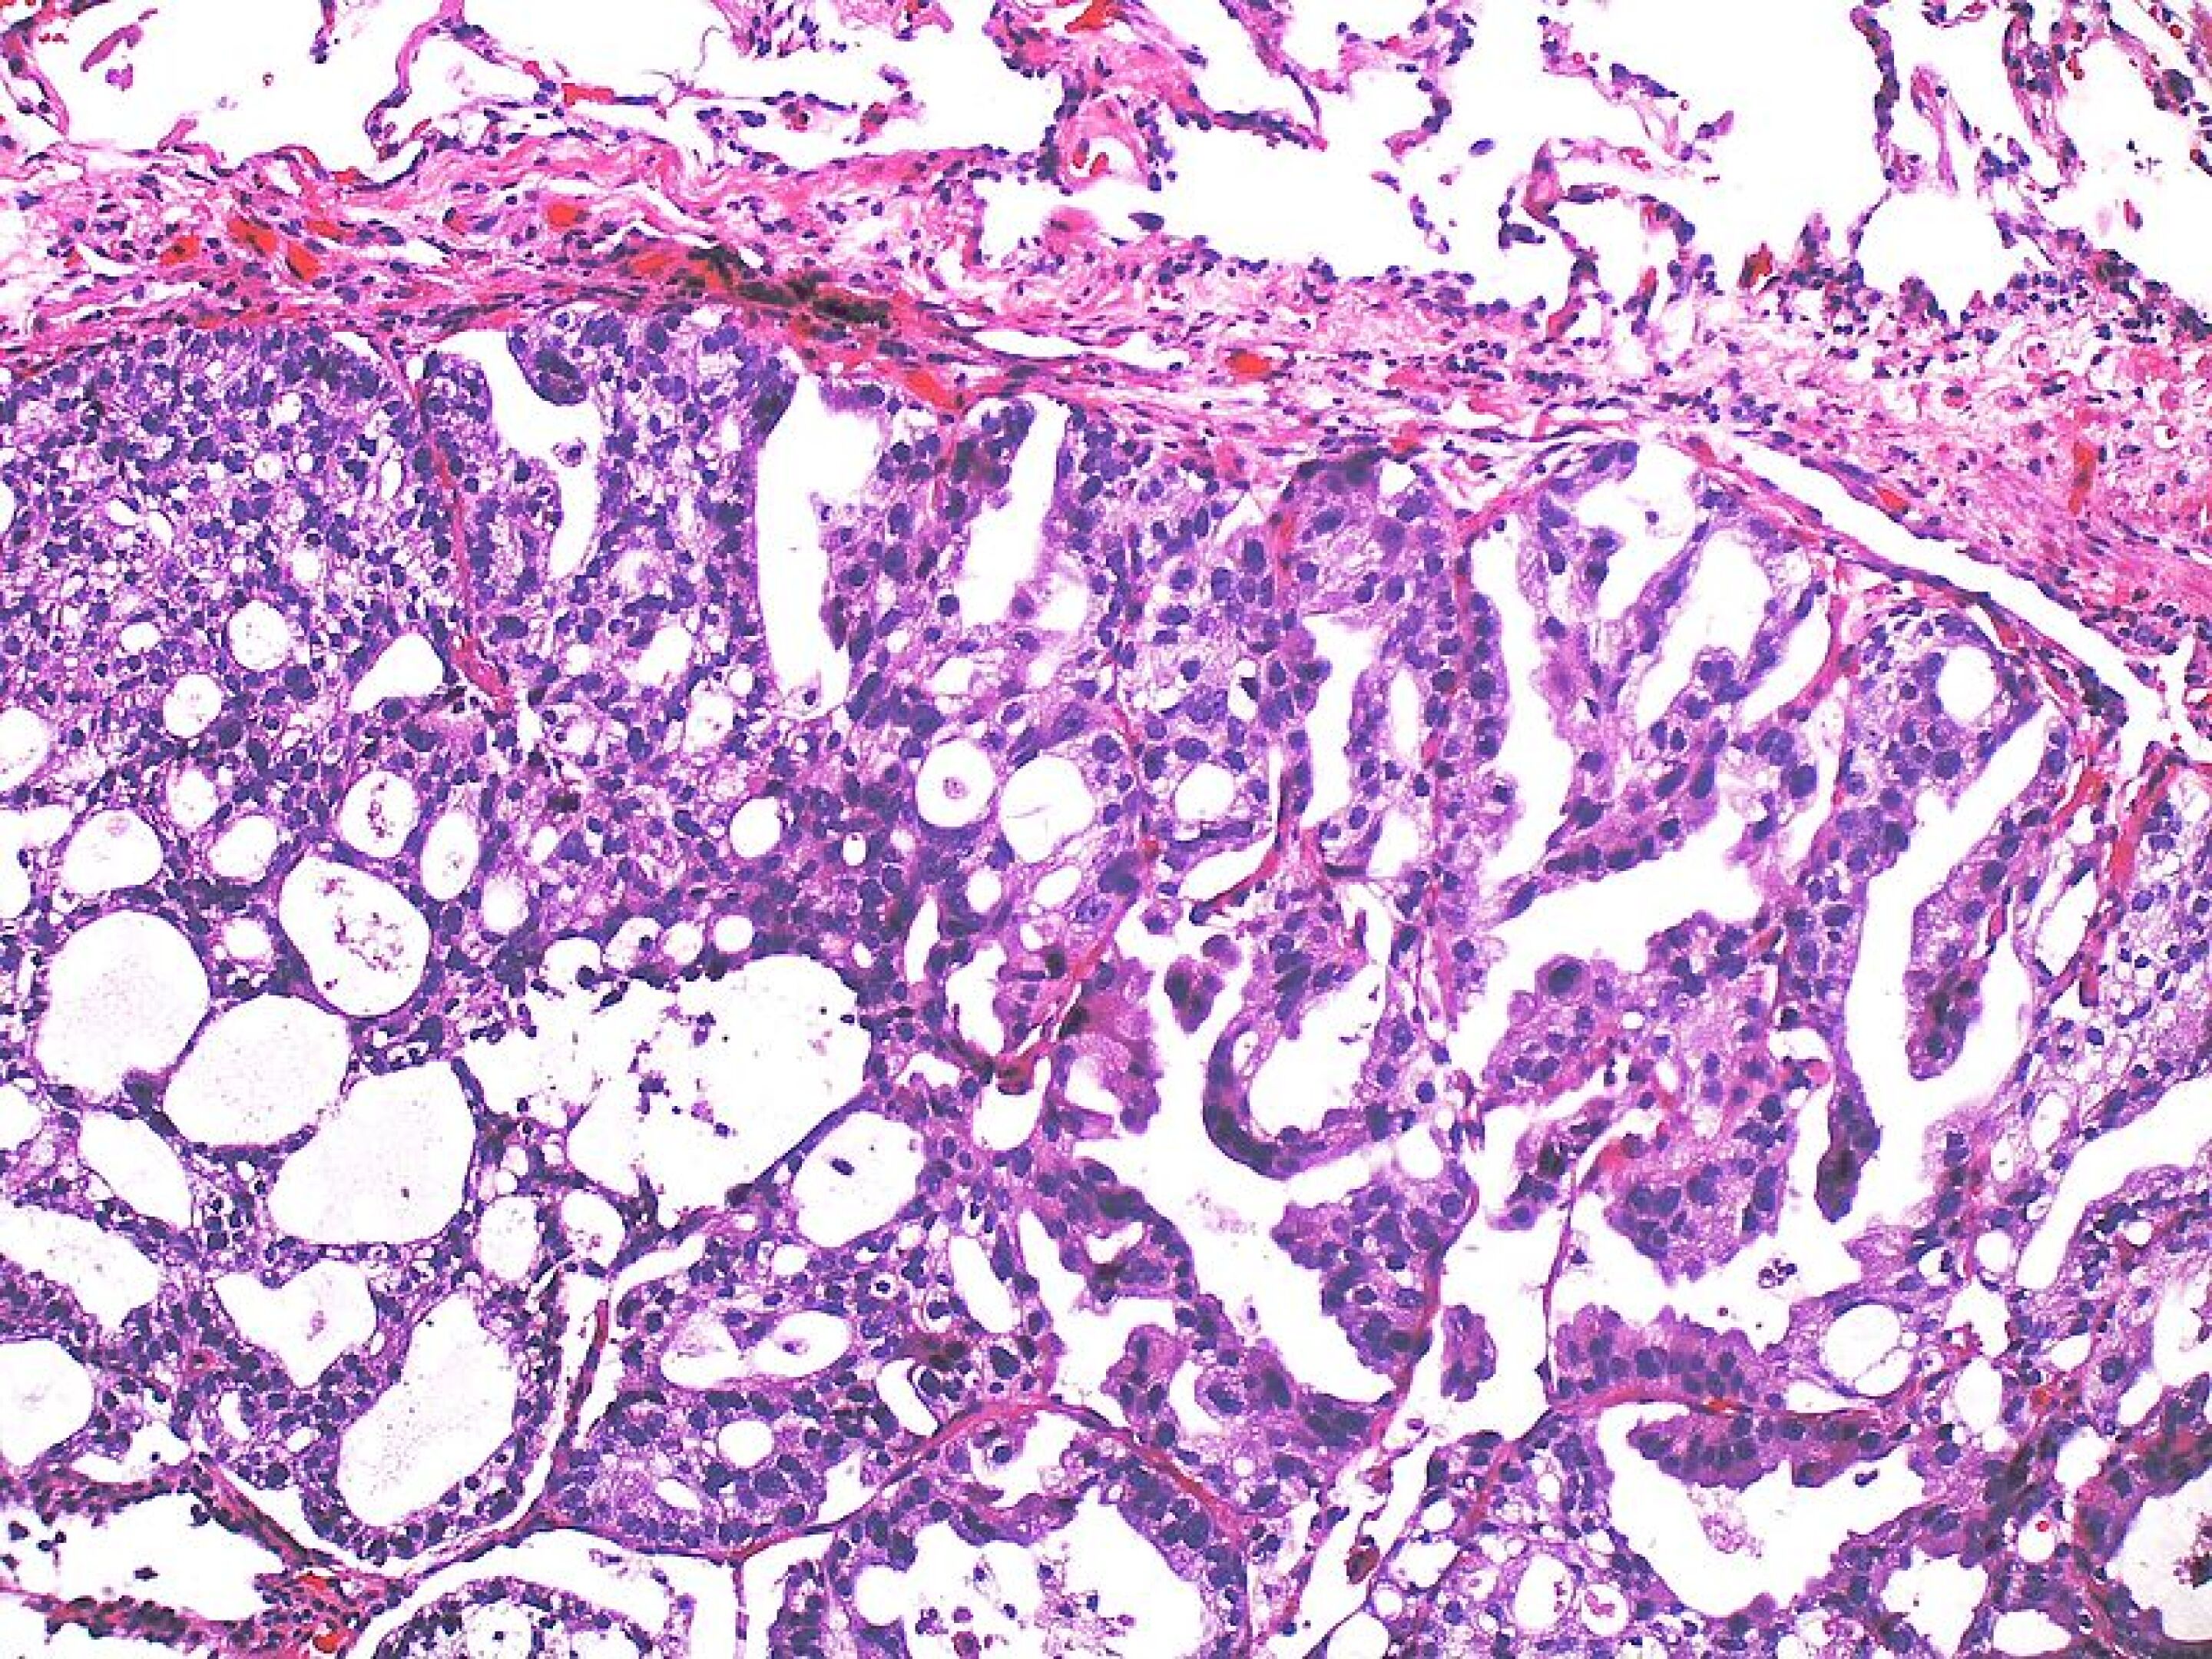

Figure 1 from Quantification of light reflectance spectroscopy and its Light Reflectance Spectroscopy Prostate light reflectance spectroscopy measures the intensity of diffusely reflected light after interaction with tissue. two techniques are light reflectance spectroscopy (lrs) that uses a broadband light source and a ccd array. light reflectance spectroscopy was performed on suspected malignant and benign prostate capsule immediately. light reflectance spectroscopy, which measure backscattered light, can be used to differentiate. Light Reflectance Spectroscopy Prostate.

Detecting positive surgical margins utilisation of light‐reflectance Light Reflectance Spectroscopy Prostate light reflectance spectroscopy was performed on suspected malignant and benign prostate capsule immediately. light reflectance spectroscopy measures the intensity of diffusely reflected light after interaction with tissue. light reflectance spectroscopy, which measure backscattered light, can be used to differentiate between malignant and. light reflectance spectroscopy analysis was performed on 17 ex vivo prostate specimens, on which. Light Reflectance Spectroscopy Prostate.

(PDF) Discriminative Spectral Pattern Analysis for Positive Margin Light Reflectance Spectroscopy Prostate light reflectance spectroscopy, which measure backscattered light, can be used to differentiate between malignant and. two techniques are light reflectance spectroscopy (lrs) that uses a broadband light source and a ccd array. light reflectance spectroscopy measures the intensity of diffusely reflected light after interaction with tissue. light reflectance spectroscopy was performed on suspected malignant and benign. Light Reflectance Spectroscopy Prostate.

(PDF) Prostate cancer detection using combined autofluorescence and Light Reflectance Spectroscopy Prostate two techniques are light reflectance spectroscopy (lrs) that uses a broadband light source and a ccd array. light reflectance spectroscopy measures the intensity of diffusely reflected light after interaction with tissue. light reflectance spectroscopy analysis was performed on 17 ex vivo prostate specimens, on which a total of 11. light reflectance spectroscopy was performed on suspected. Light Reflectance Spectroscopy Prostate.

Detecting positive surgical margins utilisation of light‐reflectance Light Reflectance Spectroscopy Prostate light reflectance spectroscopy, which measure backscattered light, can be used to differentiate between malignant and. light reflectance spectroscopy analysis was performed on 17 ex vivo prostate specimens, on which a total of 11. light reflectance spectroscopy was performed on suspected malignant and benign prostate capsule immediately. light reflectance spectroscopy measures the intensity of diffusely reflected light. Light Reflectance Spectroscopy Prostate.